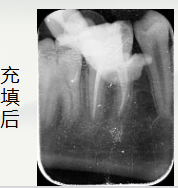

依次使用

欧罗德卡 机用锉混号 的

开口锉15/08疏通锉15103过渡锉20/05成型锉25/06